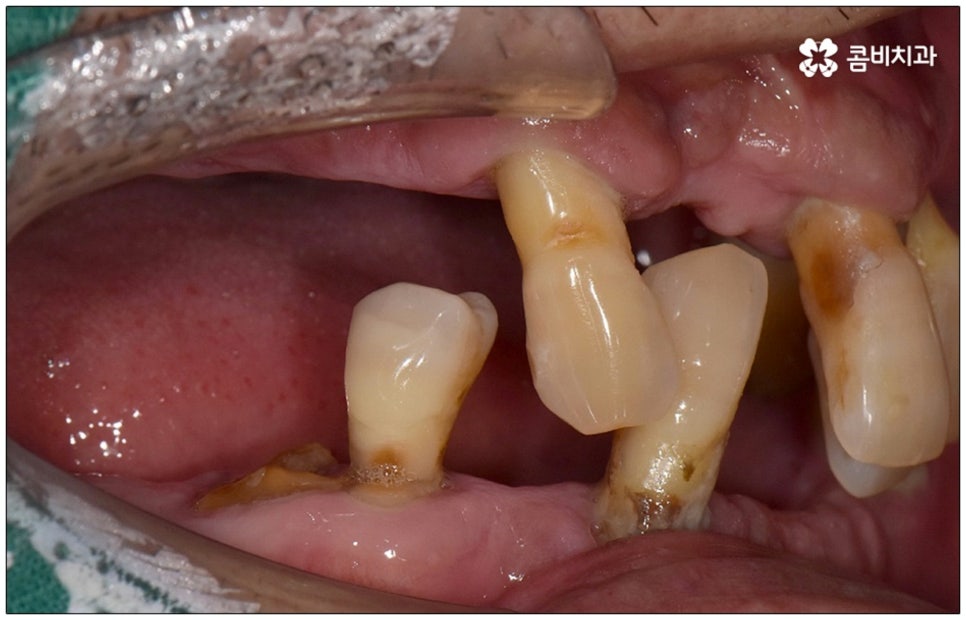

성인 이후 치아 상실의 주된 원인은 바로 풍치인데요, 풍치 즉 치주 질환은 잇몸(치은)을 포함한 치아 주위 조직에 급성 또는 만성으로 염증이 생겨서 손상이 일어난 것을 의미하고 있습니다. 이러한 풍치의 주된 원인은 치태와 치석으로, 음식물 찌꺼기와 치아 표면의 세균막(치태=플라그)이 엉겨붙어 굳어진 치석은 평상시의 칫솔질로는 제거되지 않기 때문에 스케일링 치료를 통해 주기적으로 제거해 줄 필요가 있어요. 치석이 점점 쌓이면 세균이 급증하는 온상이 되어 주변 조직에 염증이 발생하기 쉽고 병증이 심해질수록 치주인대와 치조골까지 손상이 깊어져 결국 치아가 빠지게 되는 거예요. 풍치로 치아를 잃게 되면 임플란트를 심는데도 어려움이 있기 때문에 이렇게 상황이 나빠지기 전에 제 때 적합한 치료를 받을 필요가 있어요. 하지만 잇몸의 경우 병증이 많이 깊어질 때까지 잘 알아차리기 힘든 경우가 많으므로 정기 검진 및 스케일링과 같은 평상시의 관리가 중요하다는 말씀을 드린 거예요.

임플란트 수술을 할 때는 환자의 치아 특징, 상실 원인 및 시기, 턱과 치아의 구조 및 주변 관계 등을 꼼꼼하게 파악한 뒤 식립을 진행하는데, 이와 같이 노인임플란트 수술의 경우에는 특히 현재 건강 상태를 세세하게 체크할 필요가 있으며 이때 환자분께서 고혈압이나 당뇨 등 전신 질환을 앓고 있다면 더욱 주의해야 할 거예요. 또한 평상시 환자분께서 장기 상용하는 약이 있다면 종류에 따라 지혈을 어렵게 하거나 감염의 위험성을 높일 가능성이 있는 약도 있기 때문에 필요하다면 관련 부서와 협진하여 수술 스케줄 앞뒤로 약의 복용에 대해 조정하는 등 이에 대해 정확하게 알아두는 것이 중요하므로 반드시 사전 상담을 통해 의료진에게 고지해 주시길 바라고 있습니다.

특히 다수의 치아를 상실했을 때 전체적인 교합, 골조직 및 잇몸 상태, 얼굴형과의 조화 등 모든 부분을 종합적으로 고려하여야 하며 노인임플란트 수술의 경우 다양한 변수가 발생할 수 있기 때문에 이러한 고난도 임플란트 케이스에 노련하게 대처할 수 있도록 풍부한 임상 경험과 노하우를 갖춘 의료진인지, 정밀 검진 기계를 보유하고 있는지, 처음부터 끝까지 철저한 케어 시스템을 갖추고 사후 관리까지 꼼꼼하게 진행하는지 등을 잘 살펴보시고 임플란트 수술을 진행할 치과를 신중하게 선택하시길 권유드리고 있습니다.